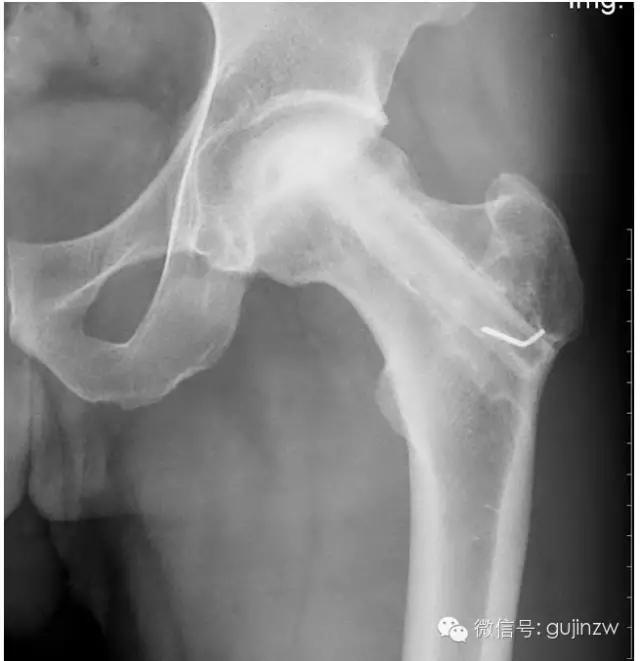

4、骨阻擋:髖關(guān)節(jié)脫位髖臼加蓋

a、適應(yīng)癥:骨缺血性壞死、一般植骨術(shù)難以奏效時(shí)。

b、要點(diǎn):吻合血管,保存血運(yùn)